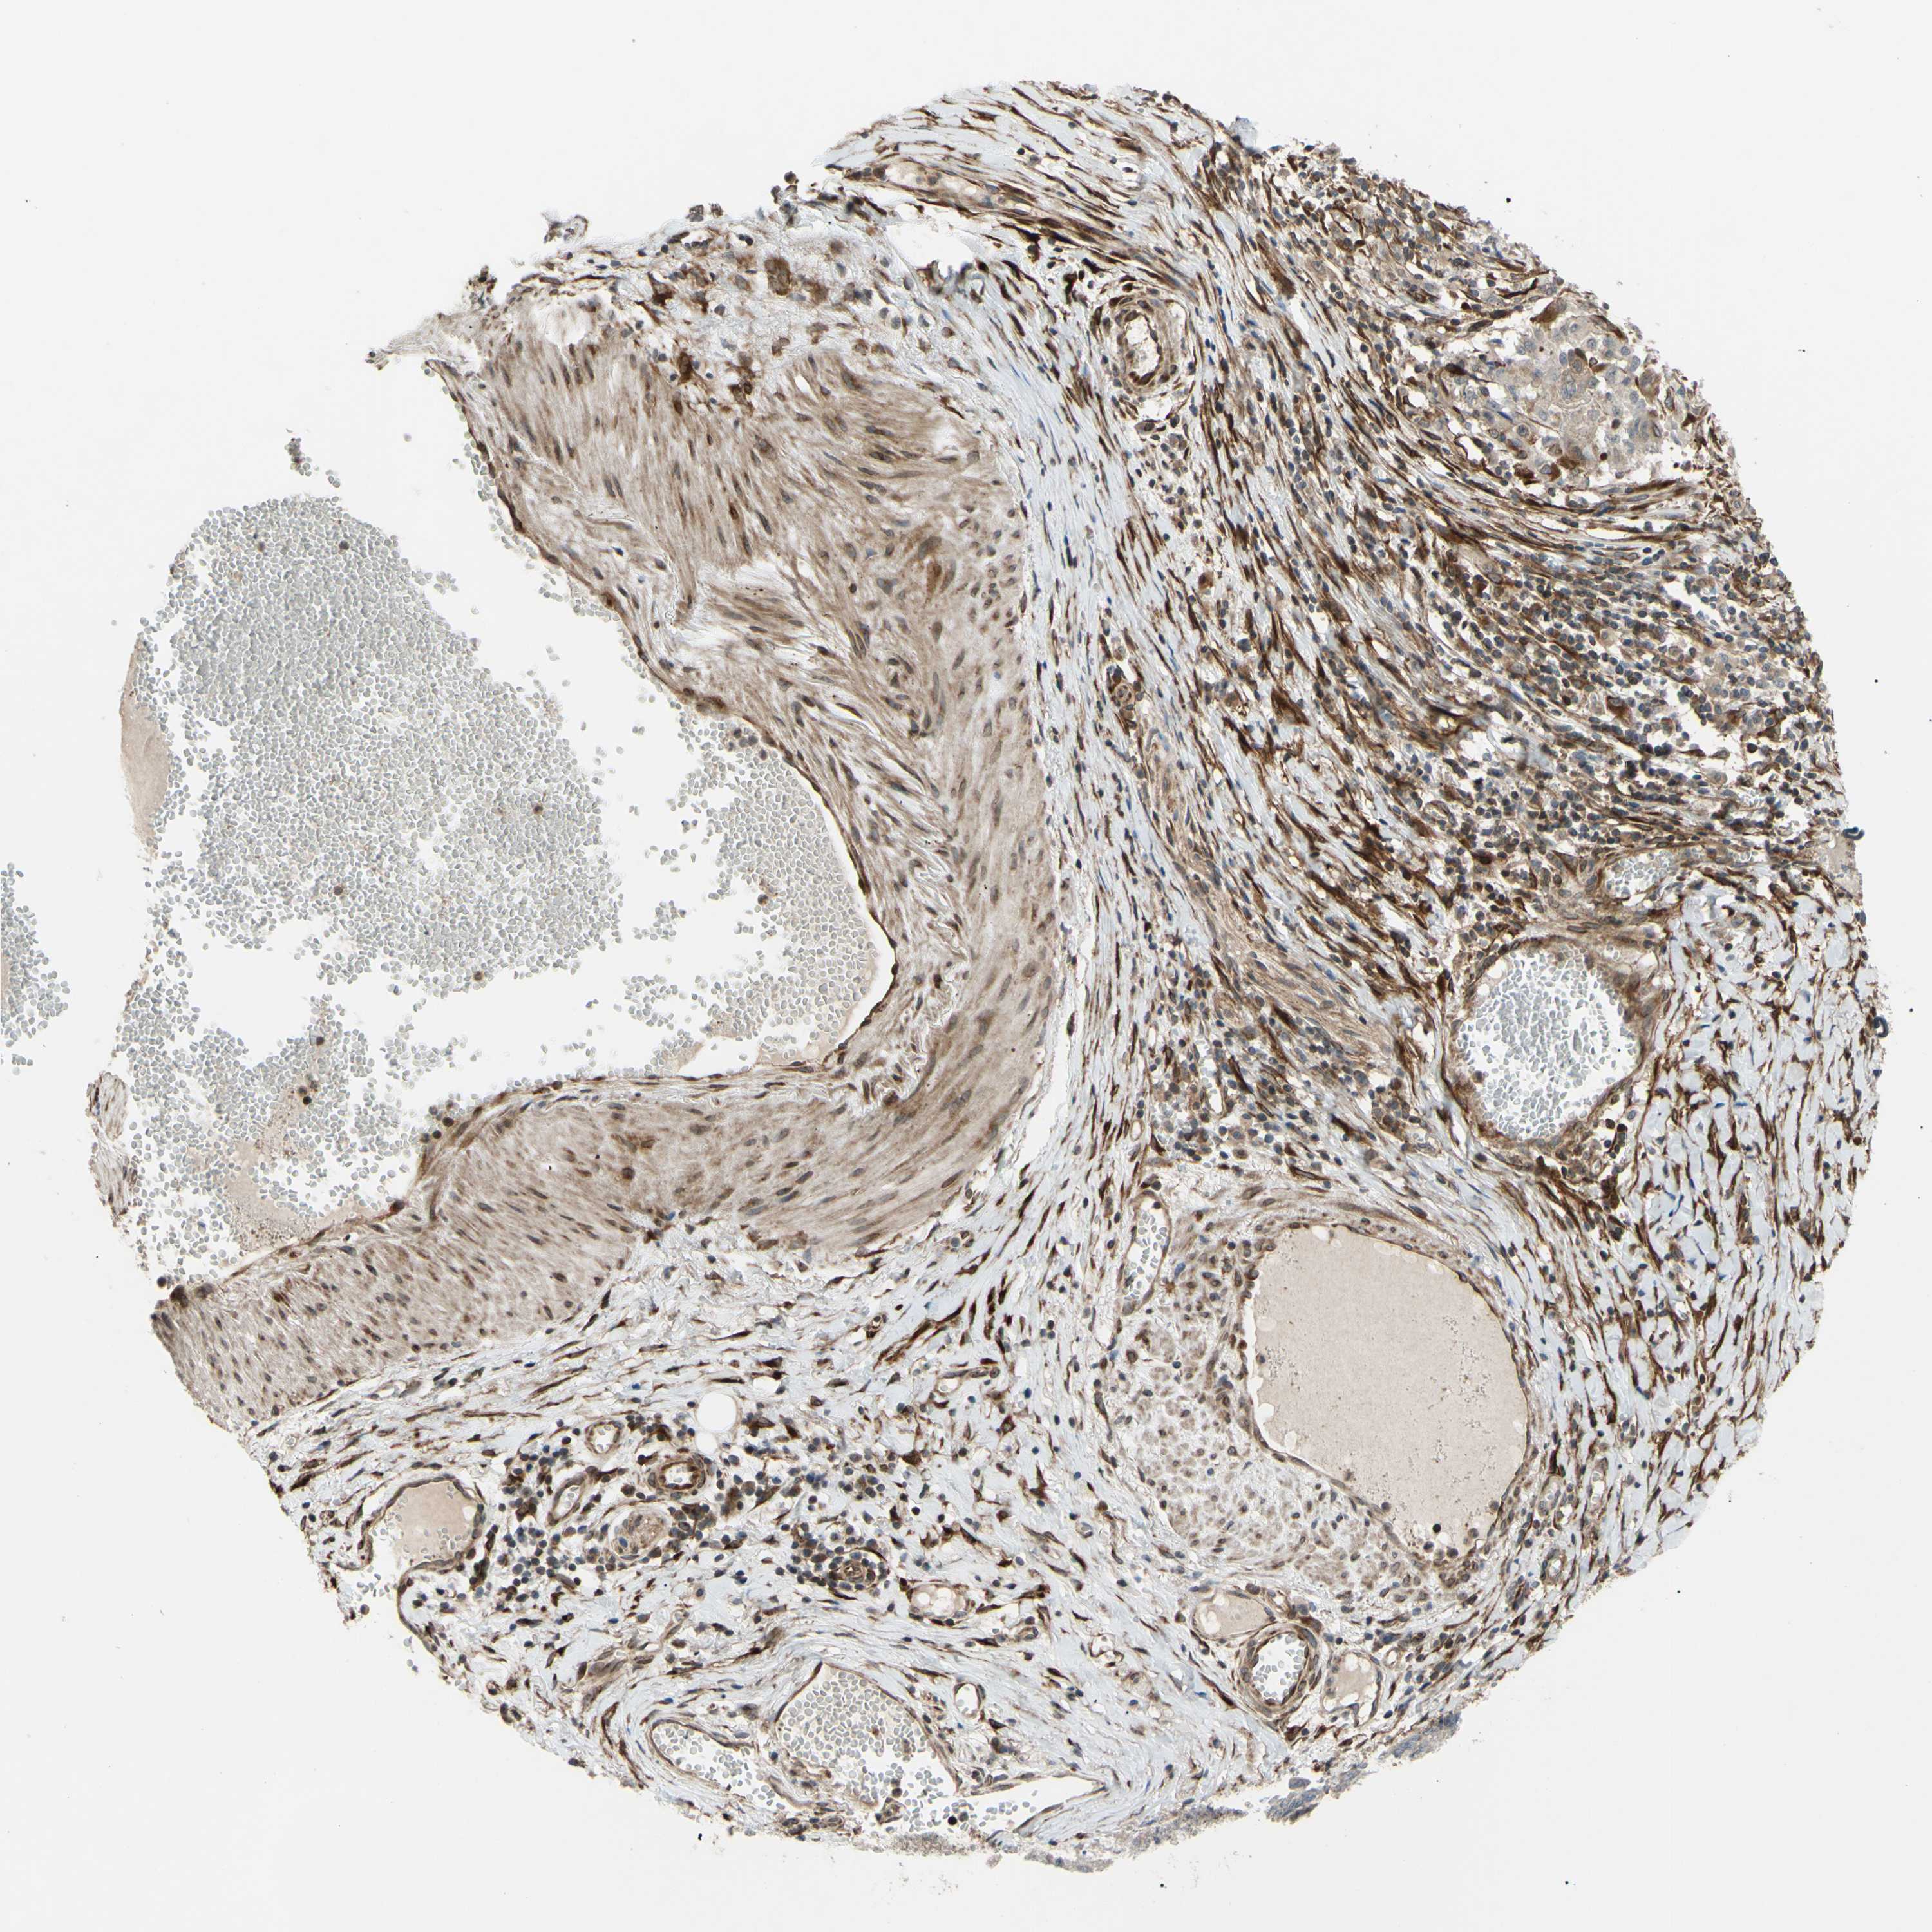

STOMACH CANCER - Protein expressioni

A mouse-over function shows sample information and annotation data. Click on an image to view it in a full screen mode. Samples can be filtered based on level of antibody staining by selecting one or several of the following categories: high, medium, low and not detected. The assay and annotation is described here.

Note that samples used for immunohistochemistry by the Human Protein Atlas do not correspond to samples in the TCGA dataset.

Antibody stainingi

Antibody staining in the annotated cell types in the current human tissue is reported as not detected, low, medium, or high, based on conventional immunohistochemistry profiling in selected tissues. This score is based on the combination of the staining intensity and fraction of stained cells.

Each image is clickable and will lead to virtual microscopy that enables deeper exploration of all samples and also displays staining intensity scores, fraction scores and subcellular localization as well as patient and tissue information for each sample.

Antibody HPA002859

Antibody CAB011655

Staining

High

Medium

Low

Not detected

Intensity

Strong

Moderate

Weak

Negative

Quantity

>75%

75%-25%

<25%

None

Location

Nuclear

Cytoplasmic/membranous

Cytoplasmic/membranous,nuclear

Adenocarcinoma, NOS

Adenocarcinoma, High grade